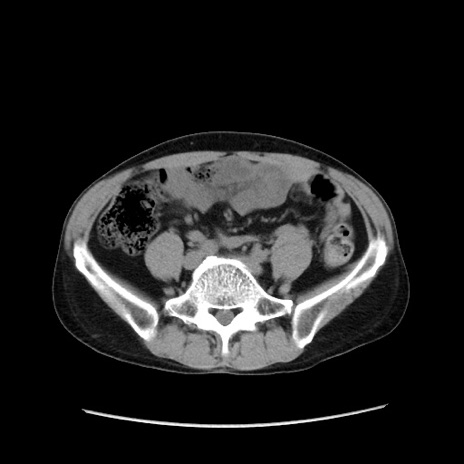

冠状断像